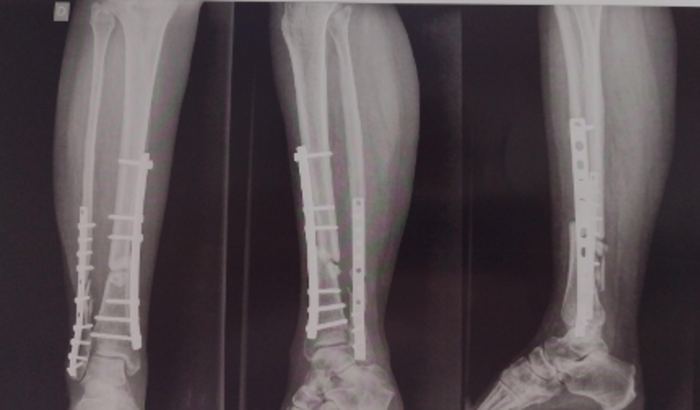

Haste intramedular na tíbia

Placa resistente na fíbula

Parafusos sem cabeça